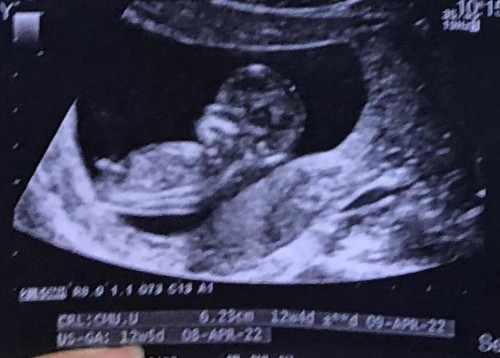

เรื่องอัลตราซาวด์

มีสิทธิ์เป็นผู้ชายมั้ยคะ หรือเป็นสายสะดือ 🥺

มีสิทธิ์คะแม่บ้านตอนไปซาวด์ดูเพศก็เป็นแบบนี้เลยพอเข้า5-6เดือนหมบอกได้ลูดชาย